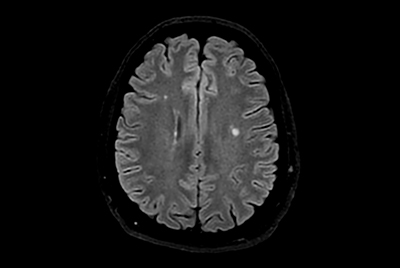

Multiple Sclerosis versus TIA

Brain Multiple Sclerosis

FLAIR* protocol for Multiple Sclerosis

Brain small infarction